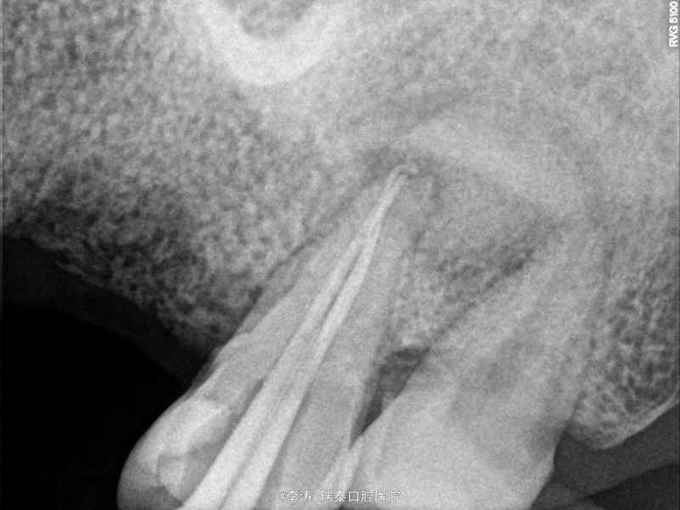

根尖区病变牙的治疗一例

牙骨质瘤 牙骨质瘤

26残冠 25,27根管治疗不到位 27牙根尖区高密度影 所有牙均无临床症状

经多方会诊,确认考虑27牙根尖牙骨质瘤,建议先行根管治疗,然后密切观察 予以拔除26,根管治疗25,27